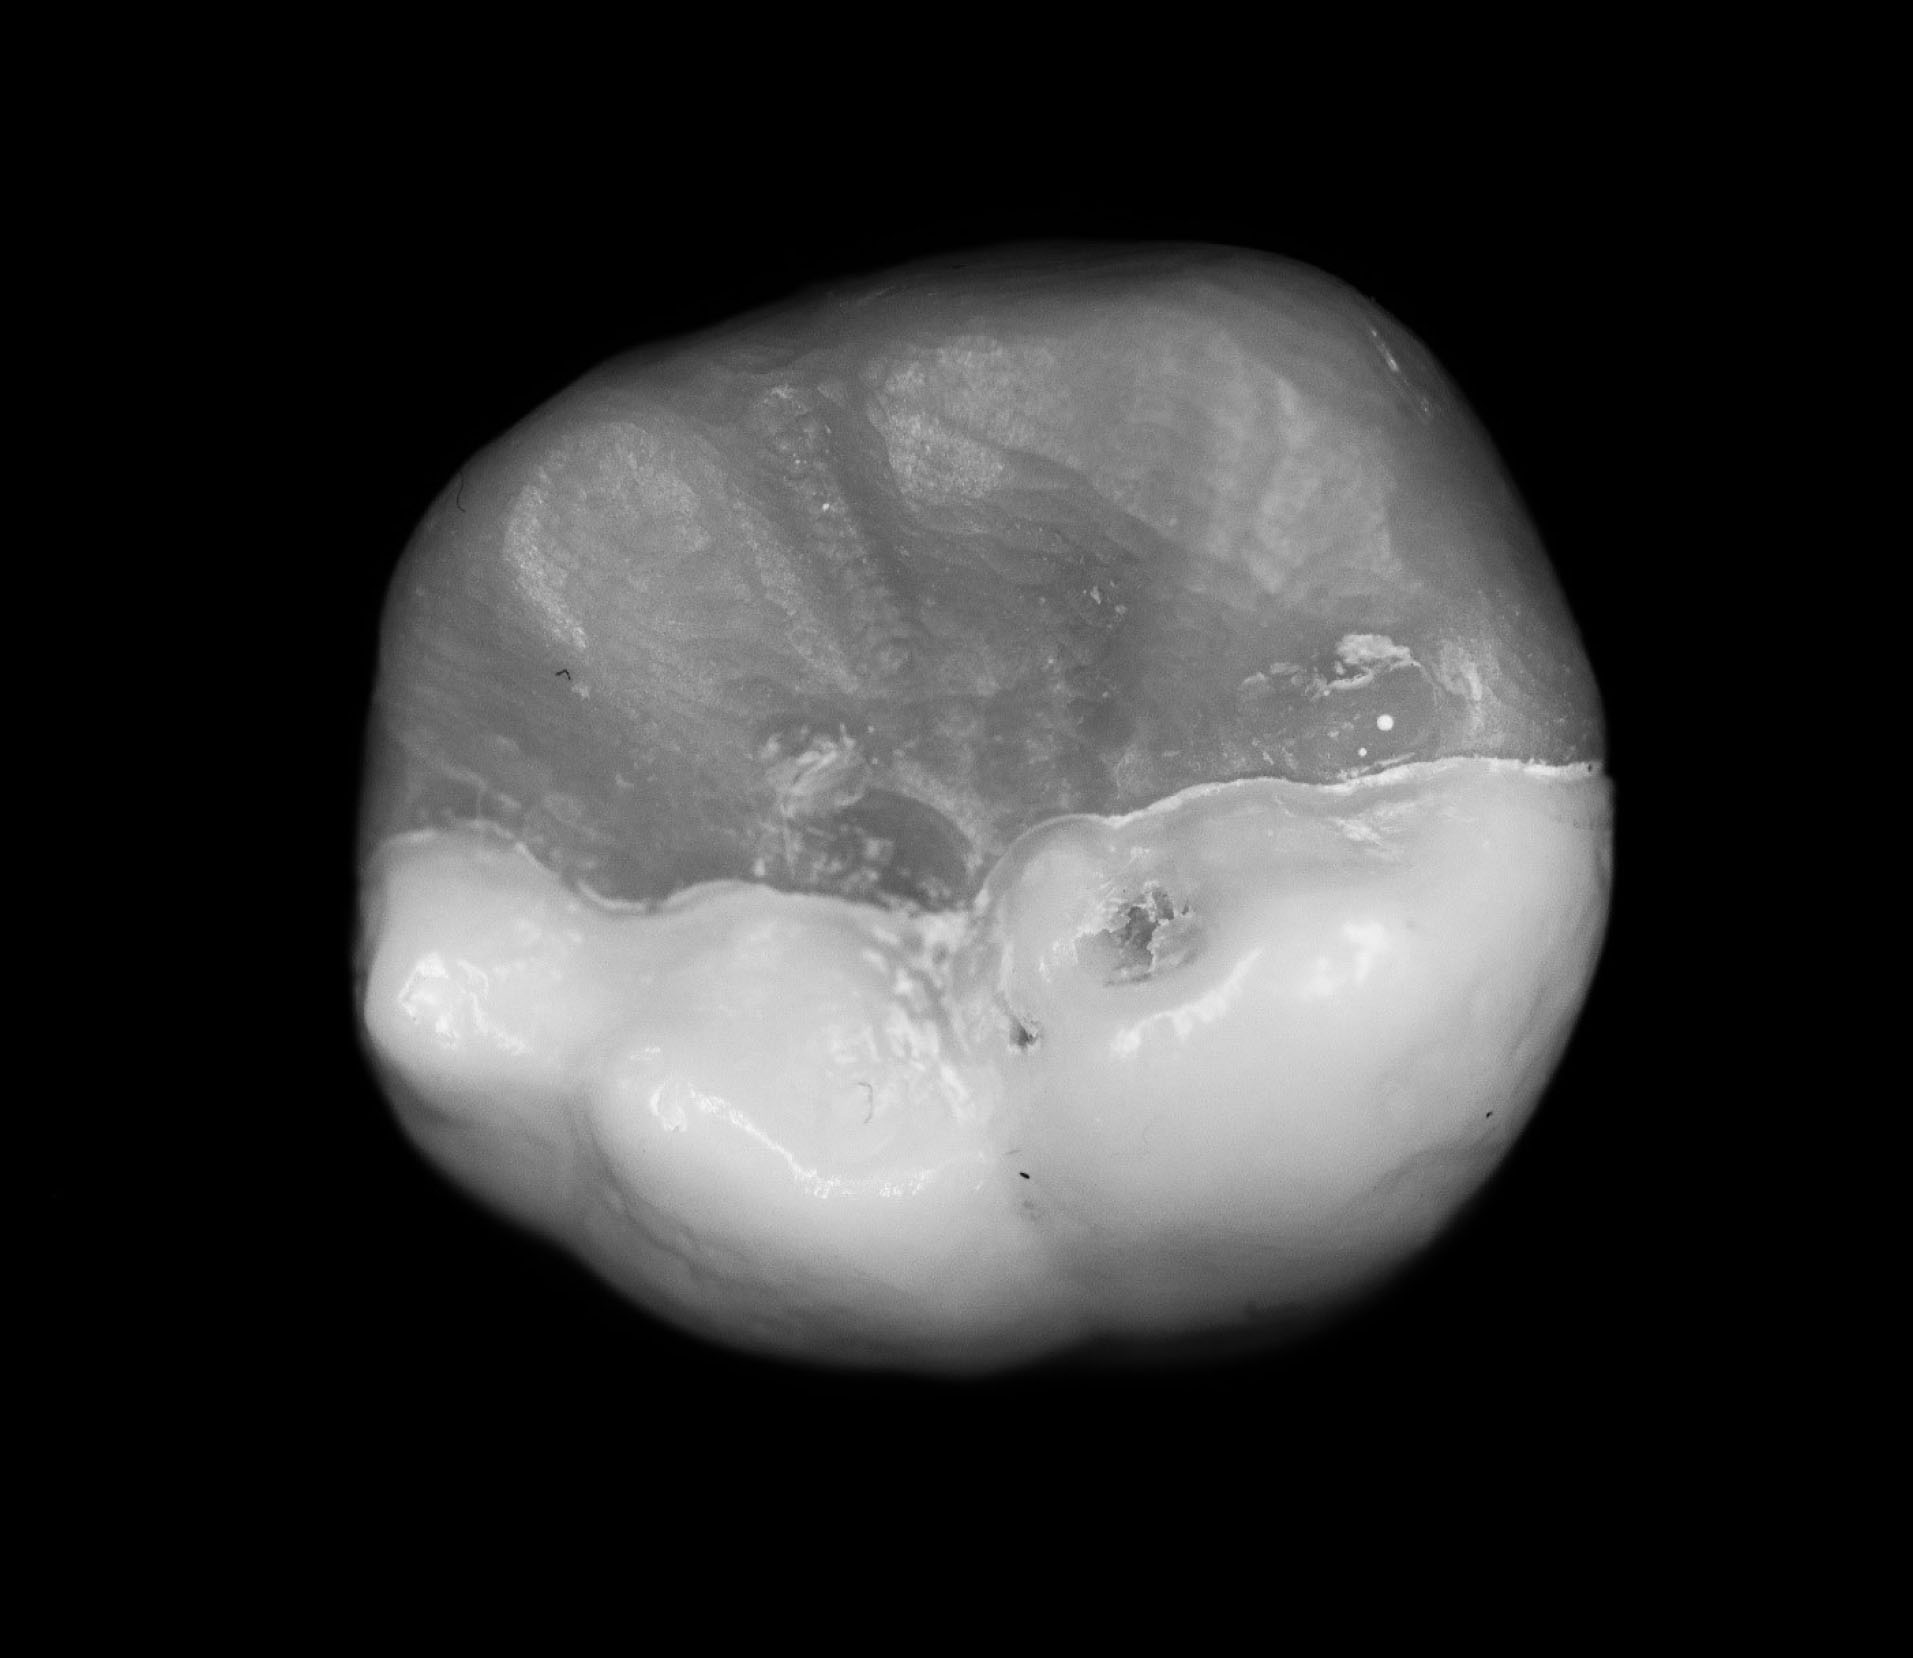

Figure 4. Occlusal view of the STL file of the onlay.

joddd-15-147-g005

Figure 5. Occlusal view of the additive-manufactured onlay.

joddd-15-147-g006

The digital scanner provided an STL file of suitable resolution for three-dimensional (3D) printing in metal. The indirect onlay restorations were successfully 3D-printed in cobalt-chromium with dimensions, morphology, and fit clinically acceptable for subsequent cementation. Cementation was unremarkable and adequately retained the onlays, similar to previous investigations. 6 Marginal adaption was generally acceptable but was clinically unacceptable in one area due to an open margin. The surface finish was generally acceptable but could be improved in some areas, especially on the occlusal surface.